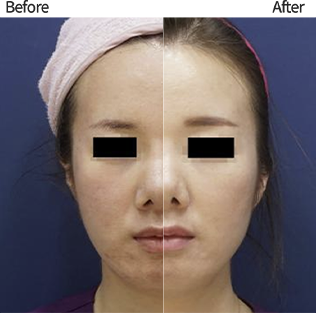

탄력 개선

탄력 개선